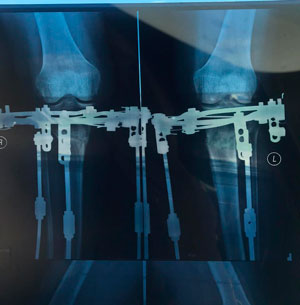

Исходник 32 года. Якутия

Дата операции - 05.02.2020г